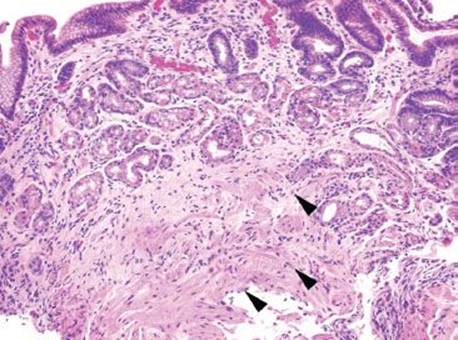

Gastric iron deposition is seen in up to 3.8% of upper tract biopsies (Fig. 2.228).23,24,183–185 In a study of 500 gastric biopsies, the deposition was demonstrated in three generalized patterns. Pattern A (also referred to as “nonspecific gastric siderosis”) was the most common subpattern and involved 2.2% of specimens (Figs. 2.229 and 2.230). This subpattern was associated with prior mucosal microhemorrhages, and the subtle depositions were predominantly identified within macrophages and stromal cells of the lamina propria. Pattern B (also referred to as “iron pill gastritis”) was seen in 0.8% of the biopsies and was consistently associated with ferrous sulfate therapy. This deposition was coarse and crystalline and predominantly identified in the extracellular and most superficial aspect of the biopsy (Figs. 2.231–2.234). In this subpattern, the background mucosa had a reactive gastritis/gastropathy pattern with erosions, ulcerations, and fibrino-inflammatory exudate common. In a separate study of 1,300 gastric biopsies, a similar “iron pill gastritis” injury pattern was detailed.184 This latter group reproduced the identical iron deposits in the laboratory by oxidizing ferrous sulfate tablets, providing clear evidence for the iron origin of these deposits. The mechanism of injury is a bit unclear in this subpattern. Some speculate that the iron pill has a direct caustic effect on the adjacent mucosa, whereas others suggest that the iron deposits may simply colonize previously injured mucosa. Pattern C (also referred to as “gastric glandular siderosis”) was the least common pattern, involving 0.6% of the specimens. This subpattern was associated with iron overload settings, such as hereditary hemochromatosis and multiple blood transfusions. The characteristic deposits were subtle, uniform, and identified in the deep antral and oxyntic glands (Figs. 2.235–2.239). The iron deposits can be highlighted blue with a Prussian blue iron special stain. Recognition is important to help prevent further injury and potential stricture formation (pattern B), to suggest pertinent iron overload evaluation (pattern C), and to avoid overdiagnosing the marked reactive epithelial change as dysplasia.

Figure 2.229 Iron pattern A/“nonspecific gastric siderosis”. This is the most common iron pattern of injury, and it can be easy to miss on low power. Scattered pigment laden macrophages and stromal cells are seen (arrowheads), characteristic of the iron pattern A/nonspecific gastric siderosis pattern. Prior mucosal damage and microhemorrhages account for these findings.